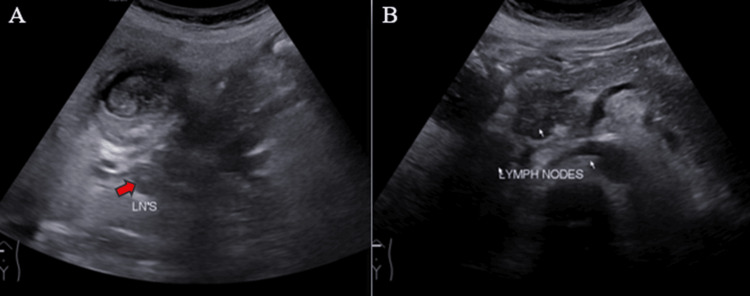

Ultrasound (US) examination revealed bilobar intrahepatic biliary radicle (IHBR) dilatation (Figure 1), and the gallbladder appeared overdistended with large, heterogeneously hypoechoic content devoid of vascularity on color Doppler (Figure 2). The gallbladder wall appeared thickened, measuringapproximately 4 mm. Furthermore, the proximal CBD appeared mildly dilated, measuring 8 mm, with a heterogeneously hypoechoic lesion within the midportion causing its narrowing (Figure 3). Multiple subcentimetric to enlarged necrotic lymph nodes were also observed in the porta-hepatis, periportal, and retroperitoneal regions (Figure 4).

These findings were suggestive of an infective etiology, likely indicative of acute cholecystitis with thick purulent content in the gallbladder and a mass lesion in the mid-portion of the CBD.